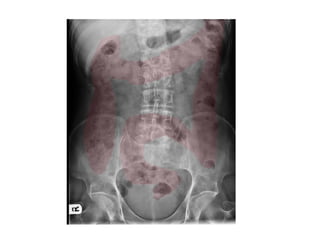

• 61 year old

female

• Previous

laparotomy

and incisional

hernia repair.

Distended

abdomen and

vomiting.

• 61 yearold female • Previous laparotomy and incisional hernia repair. Distended abdomen and vomiting.

Small Bowel Obstruction •epidemiology 1 • 80% of all mechanical bowel obstruction • average age: 64 years • females comprise 60% of patients • presentation • abdominal distension, nausea and vomiting • the level will determine the acuity of presentation • high obstruction presents early, possibly with bilious vomiting • lower obstruction presents late and may have faeculent vomiting • pathology • may be complete or incomplete • causes • adhesional SBO: occurs almost exclusively from prior surgery • herniae (often femoral or inguinal, but incisional occur) • foreign bodies or other masses, e.g. gallstones • rare: small bowel tumours causing intussusception